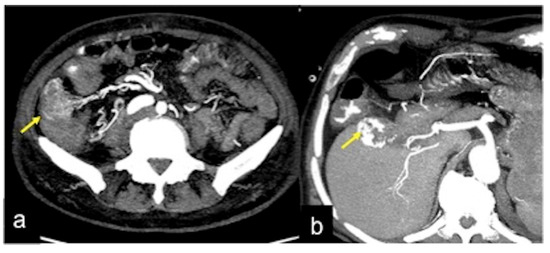

| Aorto-Enteric Fistula (Figure 31) | Bleeding in a patient with a history of surgery for aortic aneurysm. | A connection between the aorta and the intestinal lumen. Absence of adipose cleavage planes. |